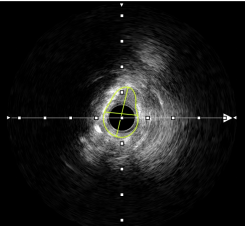

当血管内超声发现360度环形钙化,非顺应性球囊无法充分扩张病变时,选择2.5×12mm的冲击波球囊4atm即将病变充分扩张。

●疗效突破:对环形钙化及钙化结节重塑率达98%,管腔获得率较传统球囊提升40%。